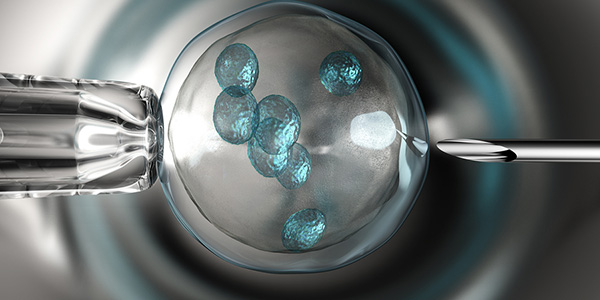

Εξωσωματική μετά τα 40 – Όλα όσα πρέπει να ξέρετε